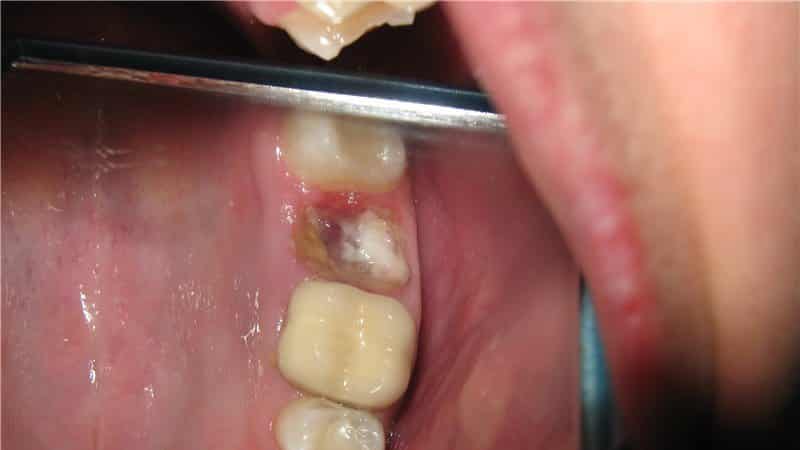

- на корне образовалась киста, которую пришлось удалять из кости;

- в процессе операции зуб сломался на несколько частей, которые врач извлекал частично;